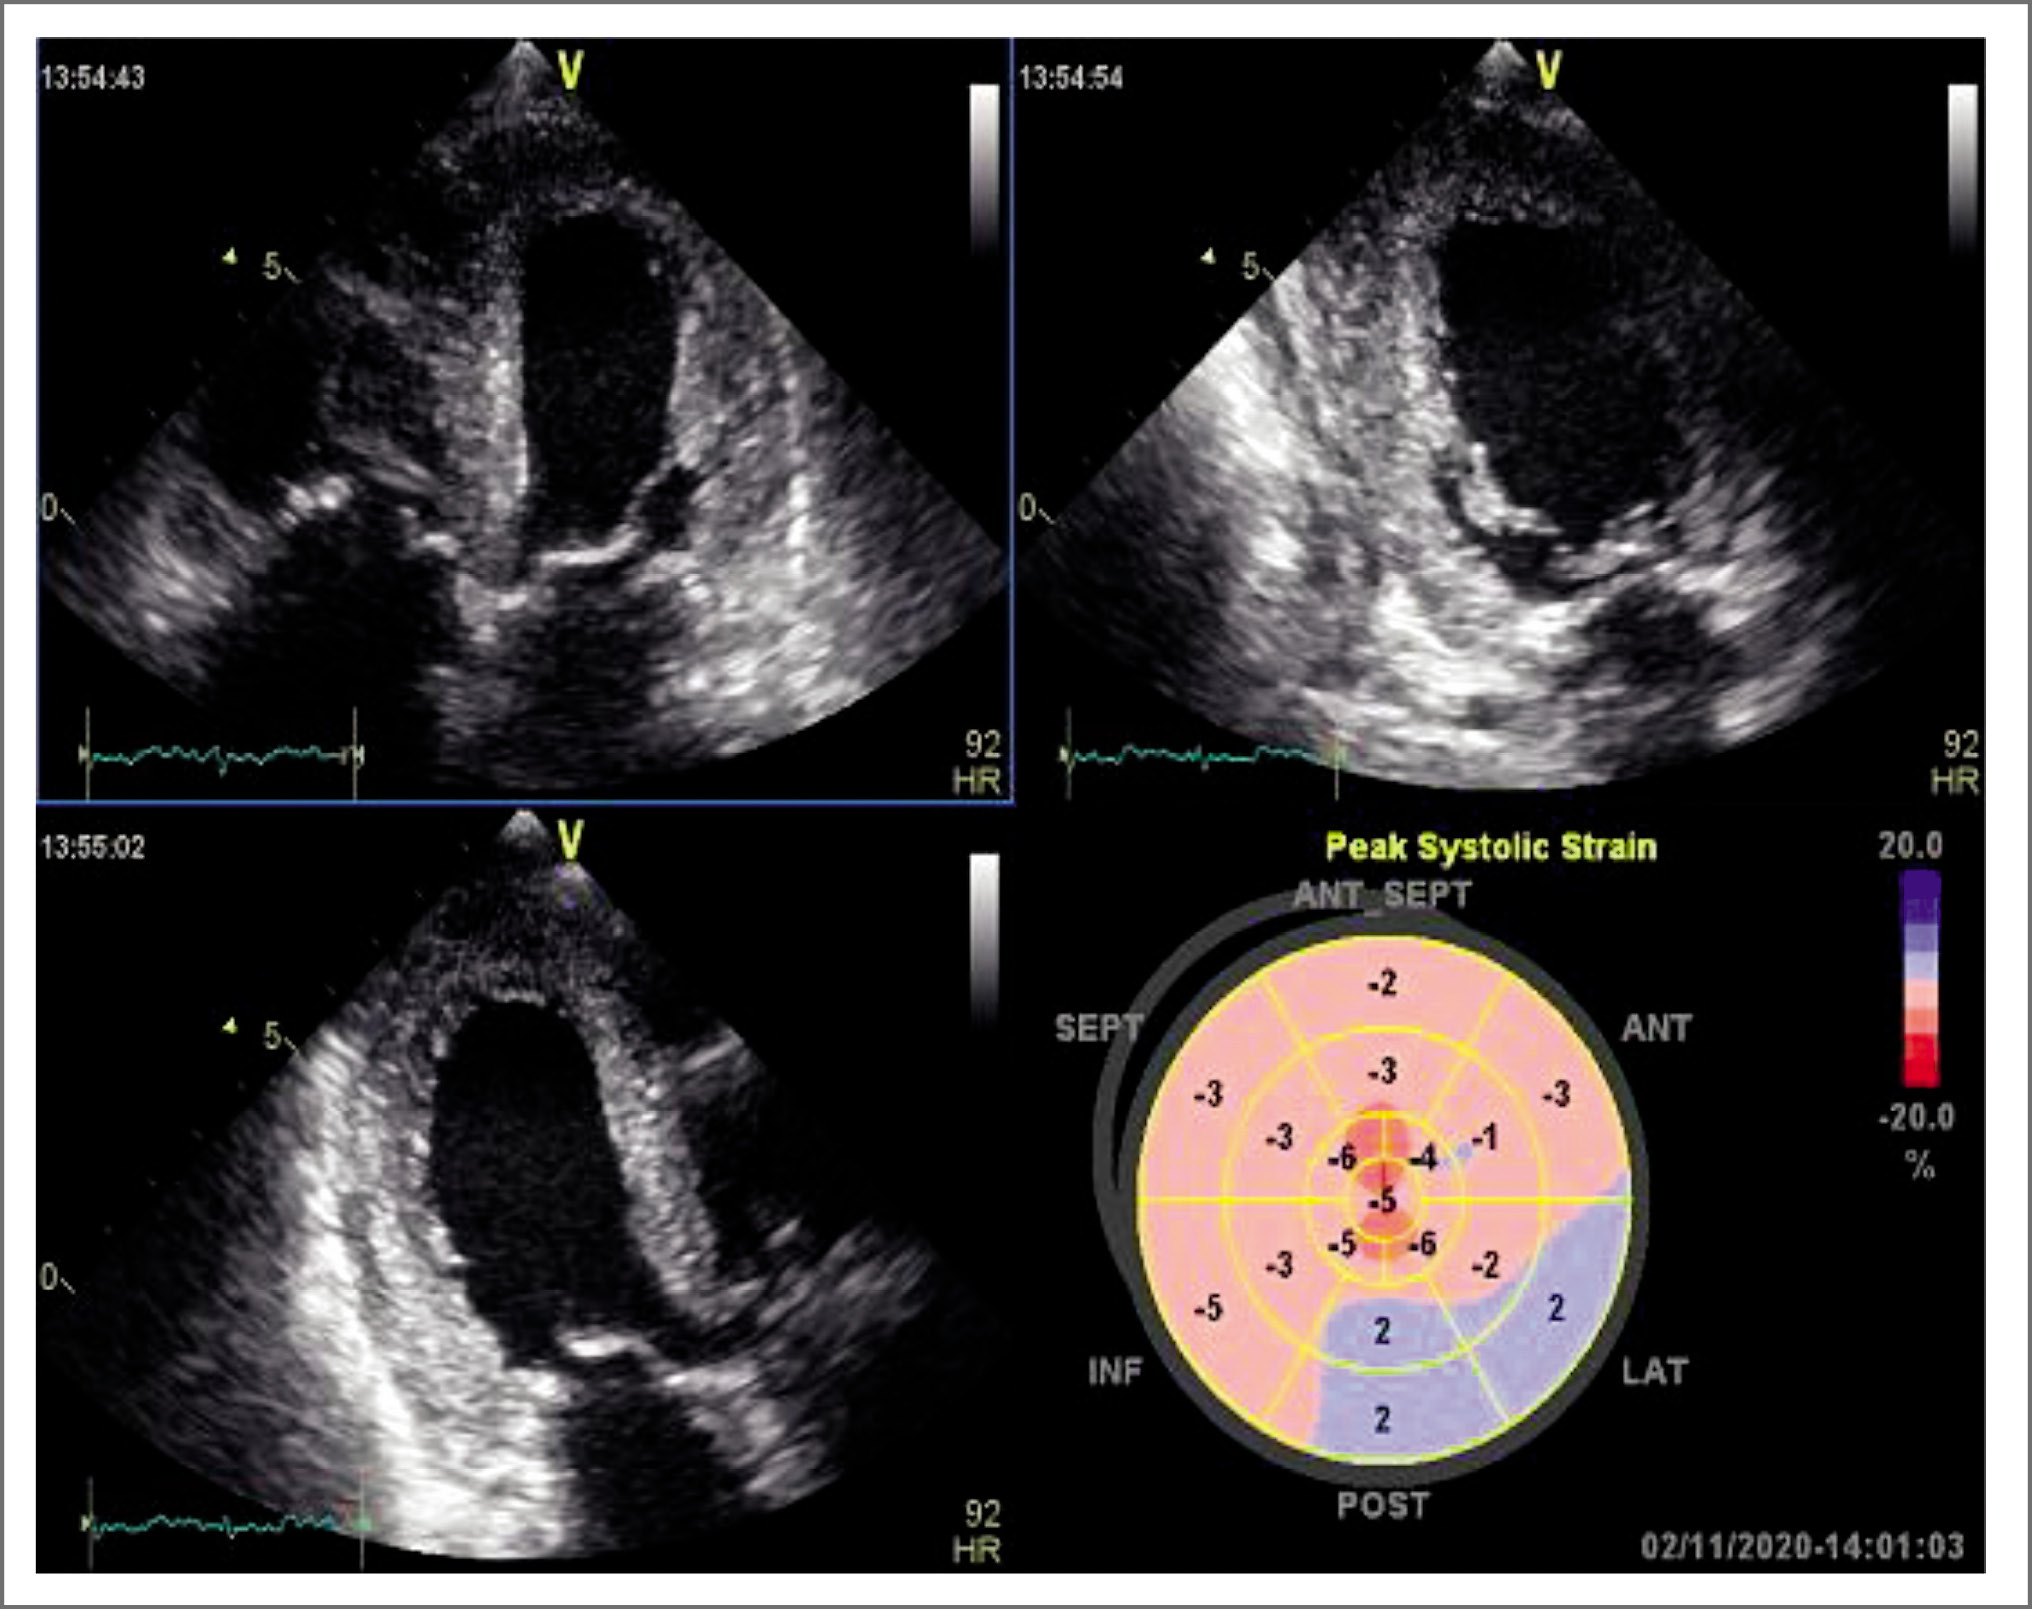

По результатам трансторакальной трехмерной ЭхоКГ: наличие гиперэхогенных включений (глыбки амилоида) в области межжелудочковой перегородки, задней стенки ЛЖ, передней стенки правого желудочка, первичной части межпредсердной перегородки, а также выраженная гиперэхогенность створок ТК и МК свидетельствуют об амилоидном поражении миокарда с вовлечением створок ТК и МК. По данным технологии Speckle-tracking ЭхоКГ (рис. 2): картина амилоидоза сердца с выраженным снижением глобальной продольной деформации -2,5% (норма <-20%) как варианта рестриктивной кардиомиопатии. В отличие от других причин гипертрофии ЛЖ отложение кардиального амилоида способствует выраженному нарушению деформации миокарда во всех исследуемых направлениях – продольном, циркулярном, радиальном [11].

Рис. 2. ЭхоКГ с технологией Speckle-tracking. Показатель глобальной продольной деформации (GLS) значительно снижен – -2,5% (N<-20%).

Fig. 2. Echocardiography with Speckle-tracking technology. Global longitudinal strain index (GLS) significantly reduced – -2.5% (N<-20%).